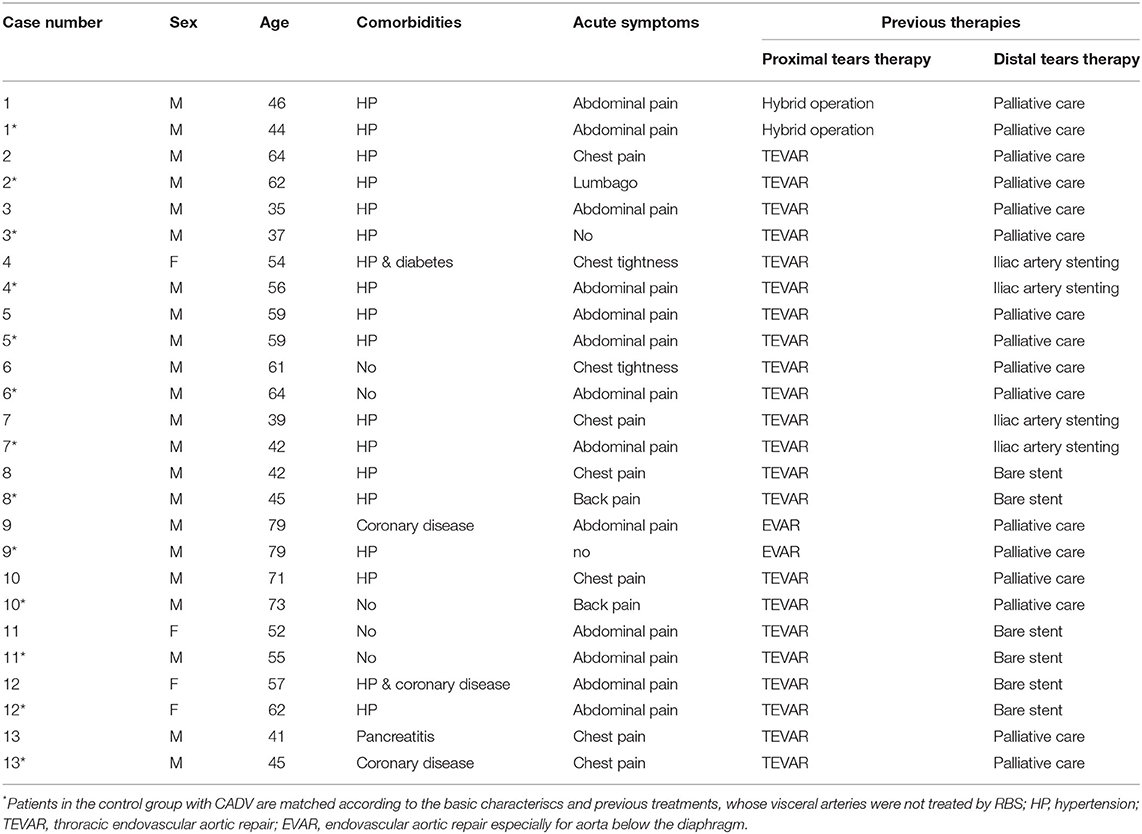

The demographic and pathological data for these 13 RBS patients and their 13 paired matched non-RBS patients are presented in Table 1. The mean age was 53.8 ± 13.1 years old for RBS patients and 55.6 ± 12.6 years for non-RBS. All patients were diagnosed with CADAV and had indications for re-intervention, as their FL expansion was observed in the abdominal visceral region or they had acute symtoms again since previous aortic repair until RBS. Their previous therapies were strictly controled; therefore, the comorbidities were hard to limit to the same. All patients previously underwent aortic repair, and 5 patients in each group presented distal dissection in the visceral segment previously been treated by endovascular techniques (bare stent or branch stent plantation).

Details of the two-step procedure for RBS are presented in Table 2. The treatments of non-RBS patients are not listed in Table 2 for their visceral region were not treated additionally and all of their treatments have been listed in Table 1. At least one visceral artery (celiac trunk, superior mesenteric artery, inferior mesenteric artery, or renal arteries) was supplied by the FL in all RBS or non-RBS patients. During the first step of RBS, covered stents were used in 8 patients (62%), bare stents in 3 patients (23%), and no stents were used to maintain visceral artery perfusion in the remaining 3 patients with only the initial tear preserved.